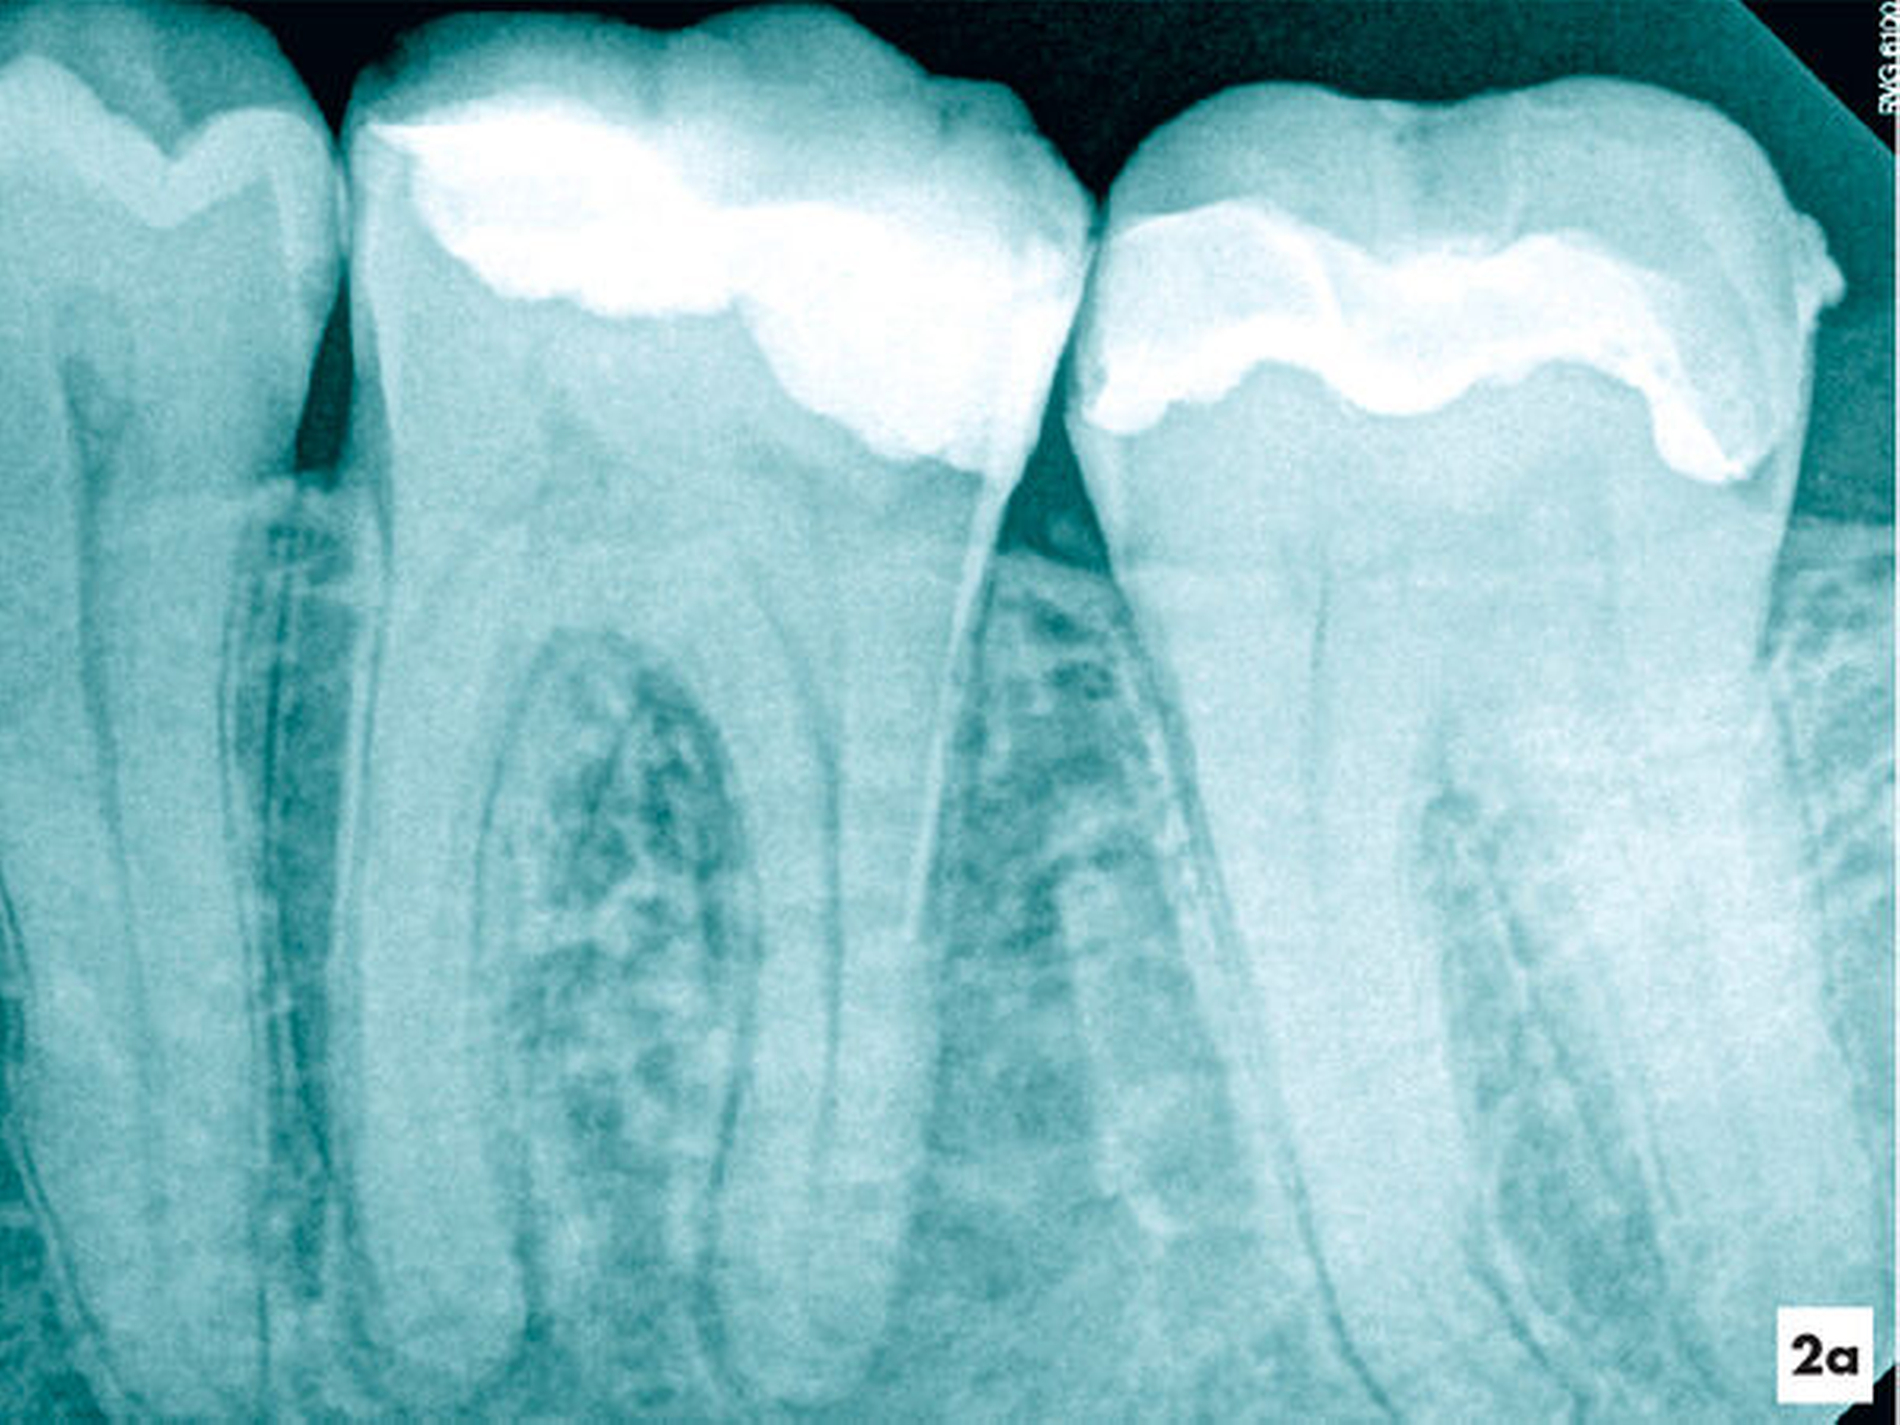

Fallbeispiel 2 (Abbildung 2)

Eine ehemals profunde Karies führte über mehrere Jahre zu einer degenerativen Pulpaerkrankung am Zahn 36. Röntgenologisch ließ sich eine Obliteration der Pulpakammer und des mesialen Wurzelkanalsystems erkennen. Distal lag eine periapikale Aufhellung vor, die klinisch mit einer Fistel assoziiert war (Abbildung 2a).

Unter absoluter Trockenlegung des Zahnes 36 mit Kofferdam erfolgte die Entfernung der Füllungsmaterialien. Im Verlauf der intrakoronalen Befundaufnahme und Diagnostik ließ sich bei 8- bis 16-facher Vergrößerung dunkel verfärbtes Dentin distal erkennen (Abbildung 2b). Innerhalb der Pulpakammer ließ sich ein dentinähnliches Hartgewebe zum Sekundärdentin differenzieren. Weichgewebige Einschlüsse am Rand ließen vermuten, dass es sich um eine reizgebundene Hartgewebeneubildung der Pulpa handelte (Abbildung 2c). Mit grazilen Rosenbohrern in absteigender Größe von ISO 012 bis 005 ließ sich das Hartgewebe sicher entfernen, so dass die mesialen Wurzelkanaleingänge für eine mechanische Erweiterung zugänglich waren (Abbildung 2d).

Während sich mesial vitales Pulpagewebe erhalten konnte, lag distal eine Pulpanekrose vor. Als Folge der Reizdentinbildung kam es auch in der distalen Wurzel zu einer Unterteilung in drei Wurzelkanäle, die bei 16-facher Vergrößerung substanzschonend erweitert, desinfiziert und gefüllt werden konnten (Abbildung 2e).

Zwei Tage nach Abschluss der einzeitigen Therapie war die Fistel verschlossen und zum 6-Monats-Recall ließ sich bereits eine deutliche Verringerung der periapikalen Aufhellung nachweisen (Abbildungen 2f und 2g).